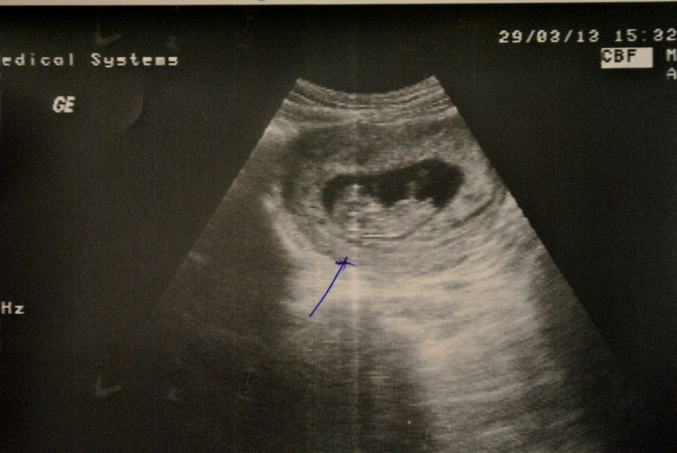

Наш первый ультразвуковой скрининг:)))

Результаты: УЗИ, КТГ, доплера, скринингаСделали сегодня

Идет у нас 11 неделя,13 акушерская:))))

ТТТ,все хорошо,все в норме

А вот и мы:)))))))))Красотка